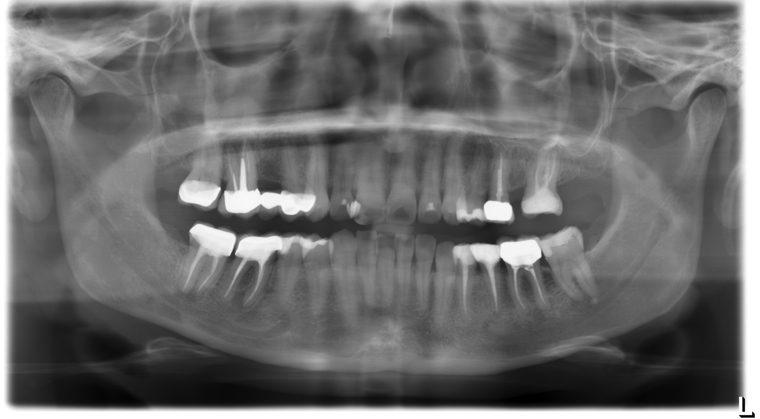

Ein Tätigkeitsschwerpunkt unserer Praxis in Salzburg ist die Implantologie. Wenn ein Zahn fehlt oder entfernt werden muss, sollte immer die Möglichkeit der Implantation im Vordergrund stehen. Ein Implantat verhält sich von den Eigenschaften genau so wie ein natürlicher Zahn. Egal ob nur ein einzelner Zahn vom Zahnarzt ersetzt werden muss oder ein ganzer Kiefer mit festsitzendem Zahnersatz versorgt werden soll, wir finden für Sie eine Möglichkeit, auch wenn die Voraussetzungen ausweglos erscheinen. Wenn möglich versorgen wir unsere Patienten mit Keramikimplantaten. Diese sind immun-neutral und können sehr oft direkt bei der Zahnextraktion eingesetzt werden. Für unsere Patienten ist daher meist nur ein operativer Eingriff notwendig!

- 3D-Röntgentechnik, 3D-Implantatplanung und virtuelle Implantation